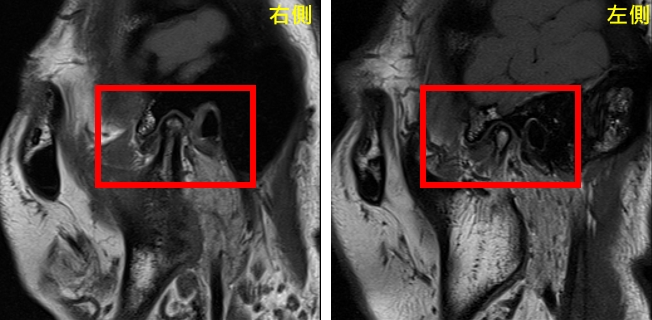

經評估,口腔顎面外科呂明怡醫師施作關節腔玻尿酸注射,搭配智慧賦能中心林志峰主任的震波治療。跨專業合作直擊病因,一個月內,曾小姐的疼痛、緊繃、喉嚨異感及肩頸不適大幅緩解,持續治療後,生活品質顯著提升,重拾自信笑容。曾小姐也分享:「過去治療都沒效,直到中山附醫團隊介入,才見曙光。希望我的經驗鼓勵病友堅持尋找適合療法。」

中山附醫口腔醫學部部長暨台灣顱顎障礙症學會理事長余權航醫師表示,此症常伴隨疼痛、咀嚼困難及頭頸不適,成因複雜,涉及關節、肌肉、咬合與壓力,需跨域整合治療。智慧賦能中心林志峰主任補充,中山附醫領先全國推動此模式,融合口腔醫學、物理治療、影像診斷及心理支持,提供全方位照護。未來將深化服務,建構臨床、教學與研究平台,陪伴患者邁向健康生活。